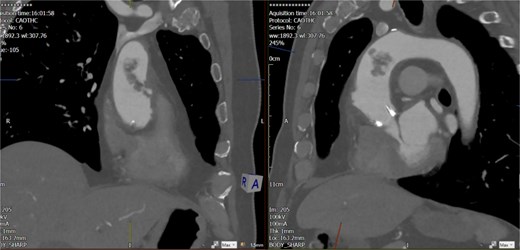

Computed tomography (CT) angiography (Figs 1 and 2) revealed a near-occlusive filling defect at the left common iliac bifurcation. Further embolic material extended into the left common femoral bifurcation, profunda femoris, and superficial femoral artery. An embolic occlusion was also present in the below-knee popliteal artery, extending to the trifurcation, with partial reconstitution of the calf vessels. Emboli were seen in the posterior tibial and peroneal arteries. On the right side, embolic material was noted in the distal profunda and popliteal artery, with further emboli in the tibio-peroneal trunk. The patient underwent bilateral femoral thromboembolectomy.

A near-occlusive filling defect at the left common iliac bifurcation. Further embolic material extended into the left common femoral bifurcation, profunda femoris, and superficial femoral artery.

Embolic occlusion of the below-knee popliteal artery extending to the trifurcation, with partial reconstitution of the calf vessels. Emboli are also present in the posterior tibial and peroneal arteries.